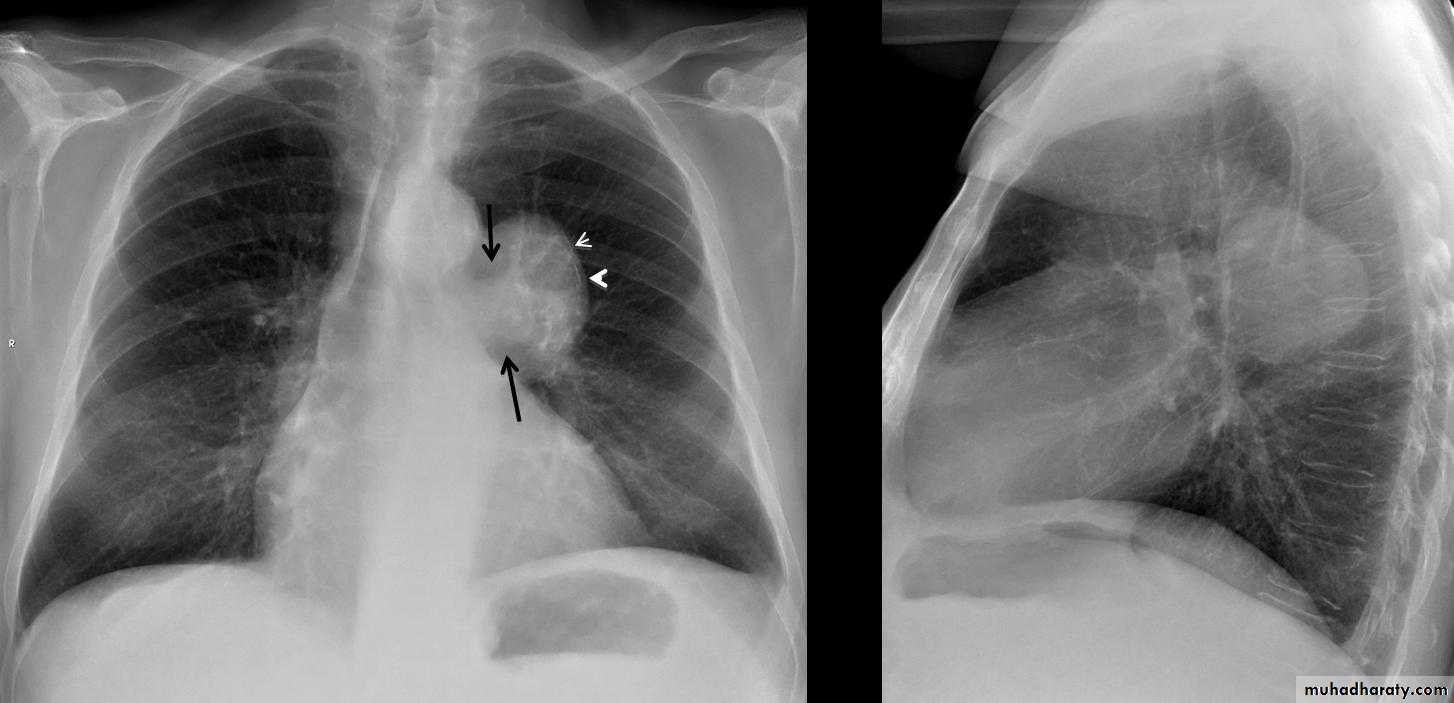

Mitral valve disease

Radiographic features

Plain film

Typical radiographic features of mitral regurgitation include :

frontal projection

1.left atrial enlargement

convexity or straightening of the left atrial appendage just below the main pulmonary artery (along left heart border)

2.double density sign: the right side of the enlarged left atrium pushes into the adjacent lung and creates an addition contour superimposed over the right heart

3.elevation of the left main bronchus and splaying of the carina

4.upper zone venous enlargement due to pulmonary venous hypertension

5.left ventricular enlargement is also eventually present due to volume overload

6.Features of pulmonary edema may also be present.